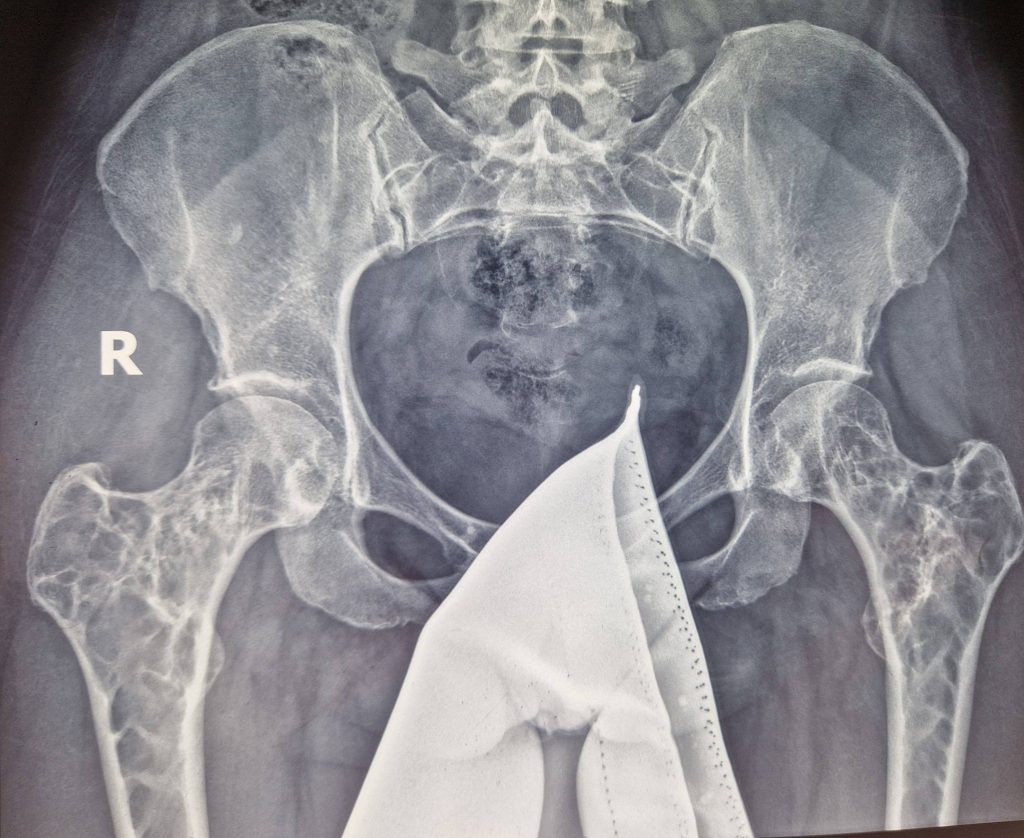

Рентгенограма аневризмальної кісти проксимального відділу обох стегнових кісток. З метою підтвердження діагнозу проведено біопсію вогнищ ураження. Наступним етапом виконано операцію видалення вогнища ураження з заповненням порожнин аллотрансплантатом, спочатку з правої, а через 6 місяців з лівої стегнової кісток. Рентгенконтроль через 6 місяців.